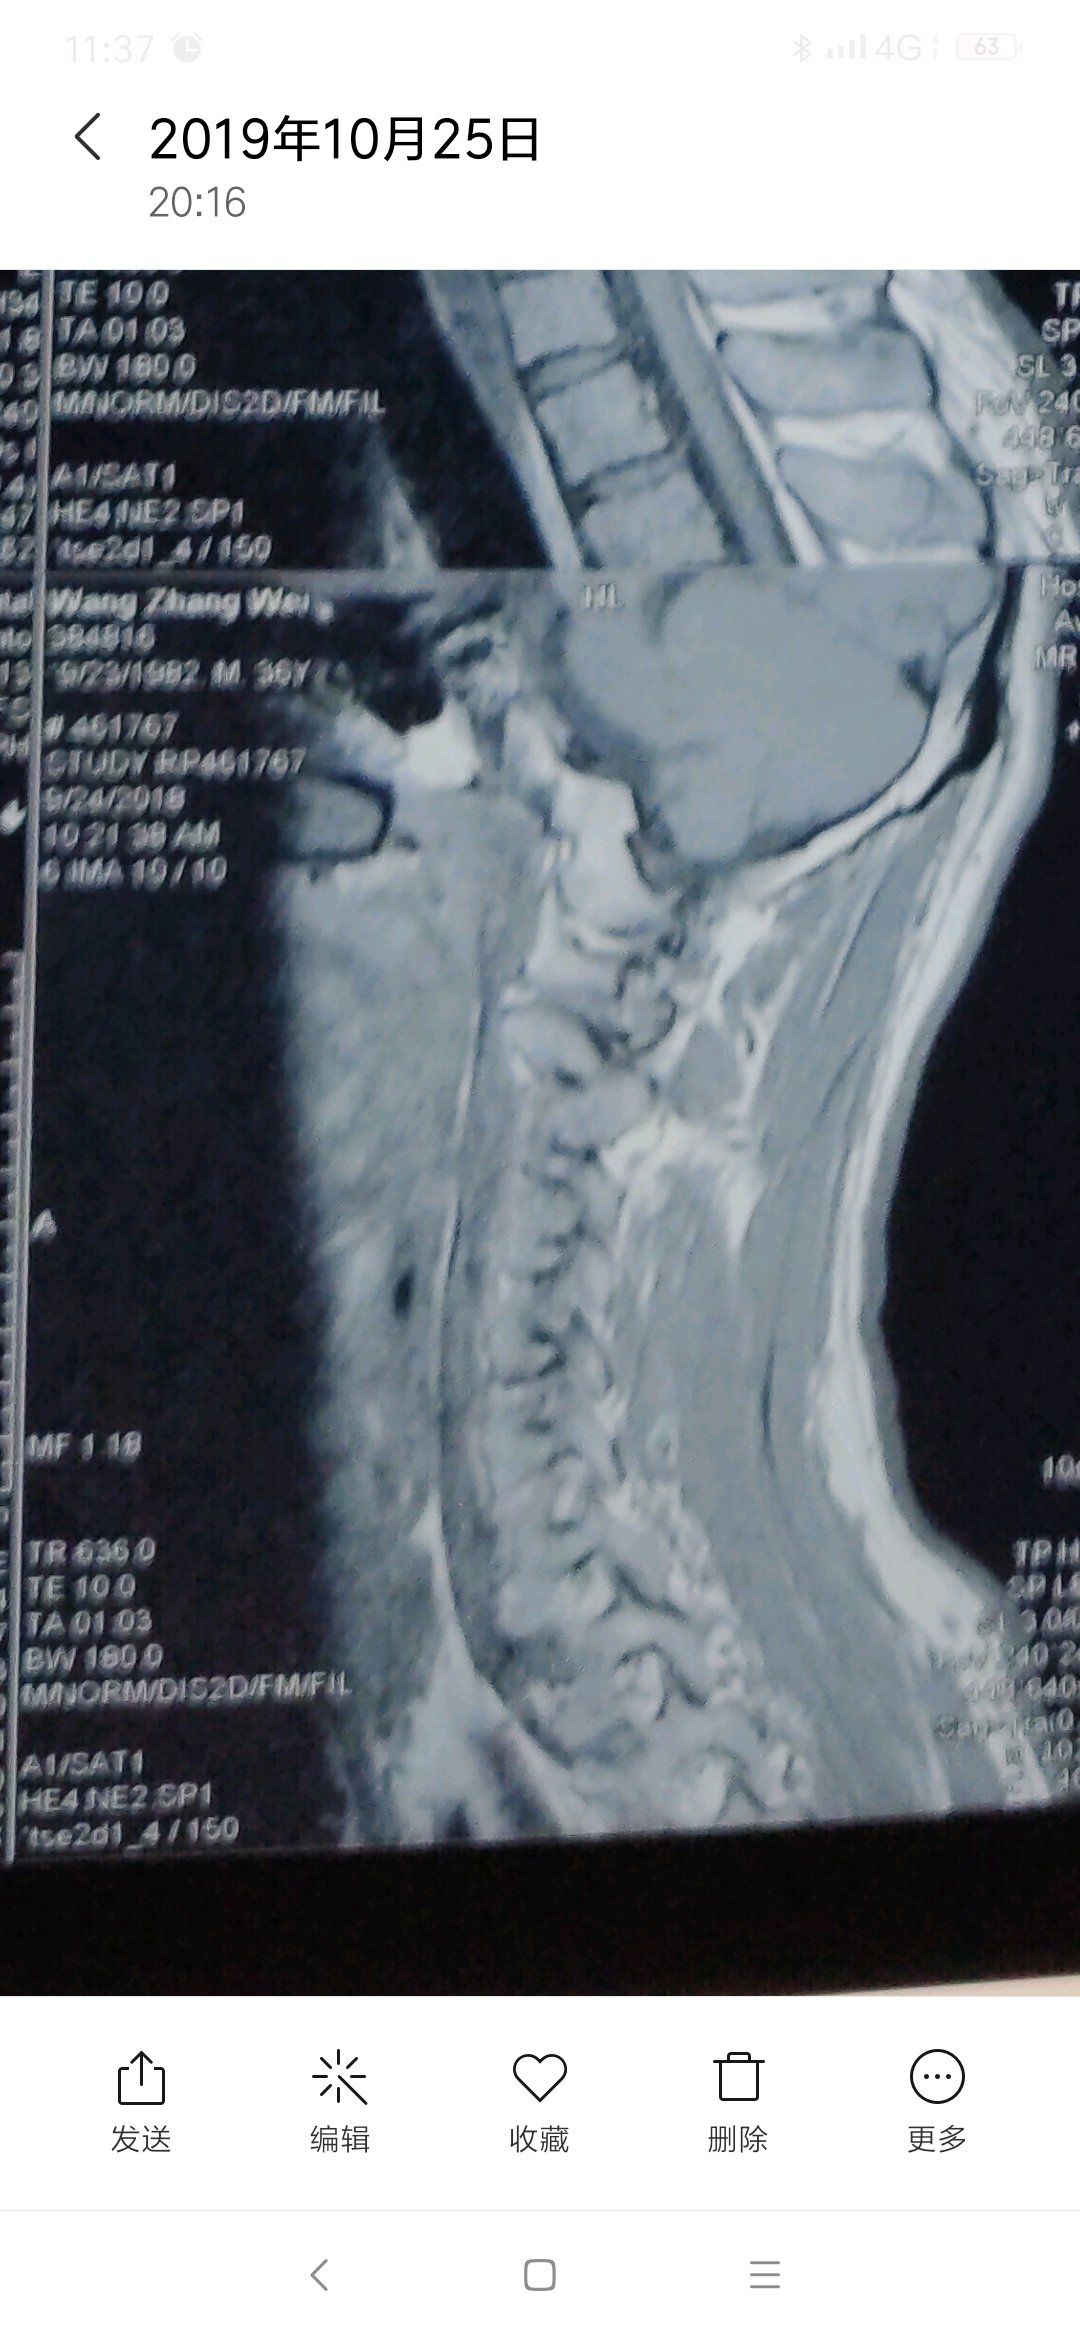

有专家吗,这个层度严重吗,怎么能治好,主要表现脖子疼痛,活动受限。

片子不严重,多锻炼就好了

每次去医院看病,医院都说不严重,可是痛起来真的太痛苦了。